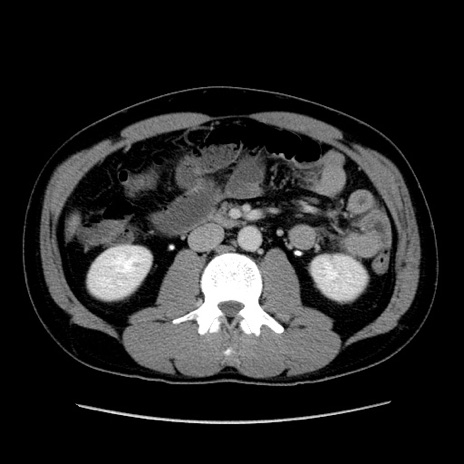

症例4(横断像)

【症例】30歳代男性

【主訴】腹痛、嘔吐

【現病歴】昨晩から突然の腹痛あり、その後嘔吐、軟便も出現。腹痛が改善しないため救急搬送となる。2日前にしめ鯖の食事歴あり。

【身体所見】意識清明、苦悶様、BP 135/90mmHg、BT 35.7℃、腹部:平坦、やや硬、心窩部〜臍部に自発痛、圧痛あり、筋性防御+、反跳痛-

【データ】WBC 8100、CRP 0.57